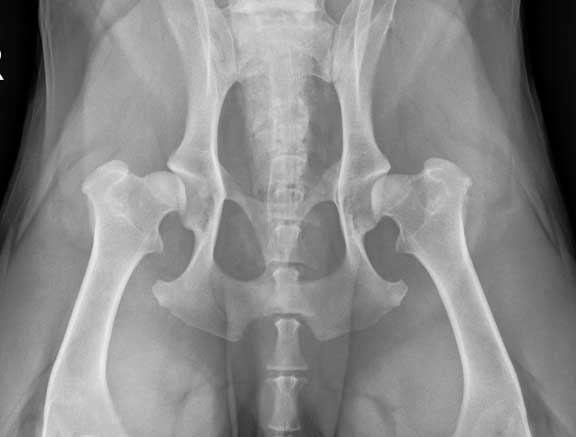

Hip Dysplasia

Labs are susceptible to hip dysplasia, a disease characterized by malformation in the hip socket, which eventually causes arthritis. The symptoms of this disease can vary, from a pet that is just not as active as it should be, to a dog that can barely get up after laying down.

These hips are dysplastic

Our hip dysplasia page has a detailed analysis of this problem that you should learn about if you are contemplating adding a golden to your family.